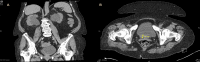

Malakoplakia is a chronic inflammatory condition that affects multiple systems, most commonly the urogenital tract. Its clinical presentation is often non-specific, but is typically characterized by recurrent urinary tract infections and haematuria. We report a rare case of intravesical malakoplakia mimicking an aggressive transitional cell carcinoma both in its clinical presentation and in its macroscopic appearance on cystoscopy in an 82-year patient, the oldest reported case in the literature. Malakoplakia has been described in the literature as a benign disease process presenting typically in younger patients. This case demonstrates its ability to cause obstructive uropathy and affect elderly patients. Thus, this case serves as a reminder to consider malakoplakia as a differential in the evaluation of suspected bladder malignancy in patients of all ages.